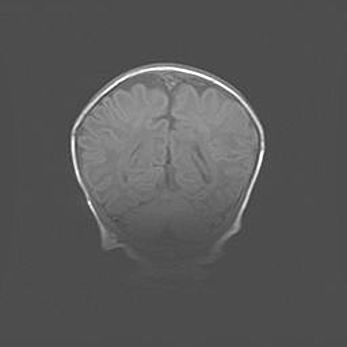

Открытая гидроцефалия.

Возраст: 6 месяцев 15 дней

Вес: 6200 г

Пол: женский

Окружность головы: 41 см

Срок гестации: 38 недель

Гидроцефалия головного мозга у новорожденных – это скопление избыточного количества цереброспинальной жидкости в головном мозге. Ее избыточное скопление в мозге приводит к патологическому расширению желудочков мозга (четырех полостей, расположенных в глубине белого вещества мозга, заполненных цереброспинальной жидкостью и связанных узкими проходами).

Открытый тип гидроцефалии (сообщающаяся) наблюдается тогда, когда нарушен механизм всасывания ликвора в системный кровоток. При этом типе причиной заболевания чаще всего является перенесенные ранее инфекции (например: менингит),  либо же наличие крови в субарахноидальном пространстве.